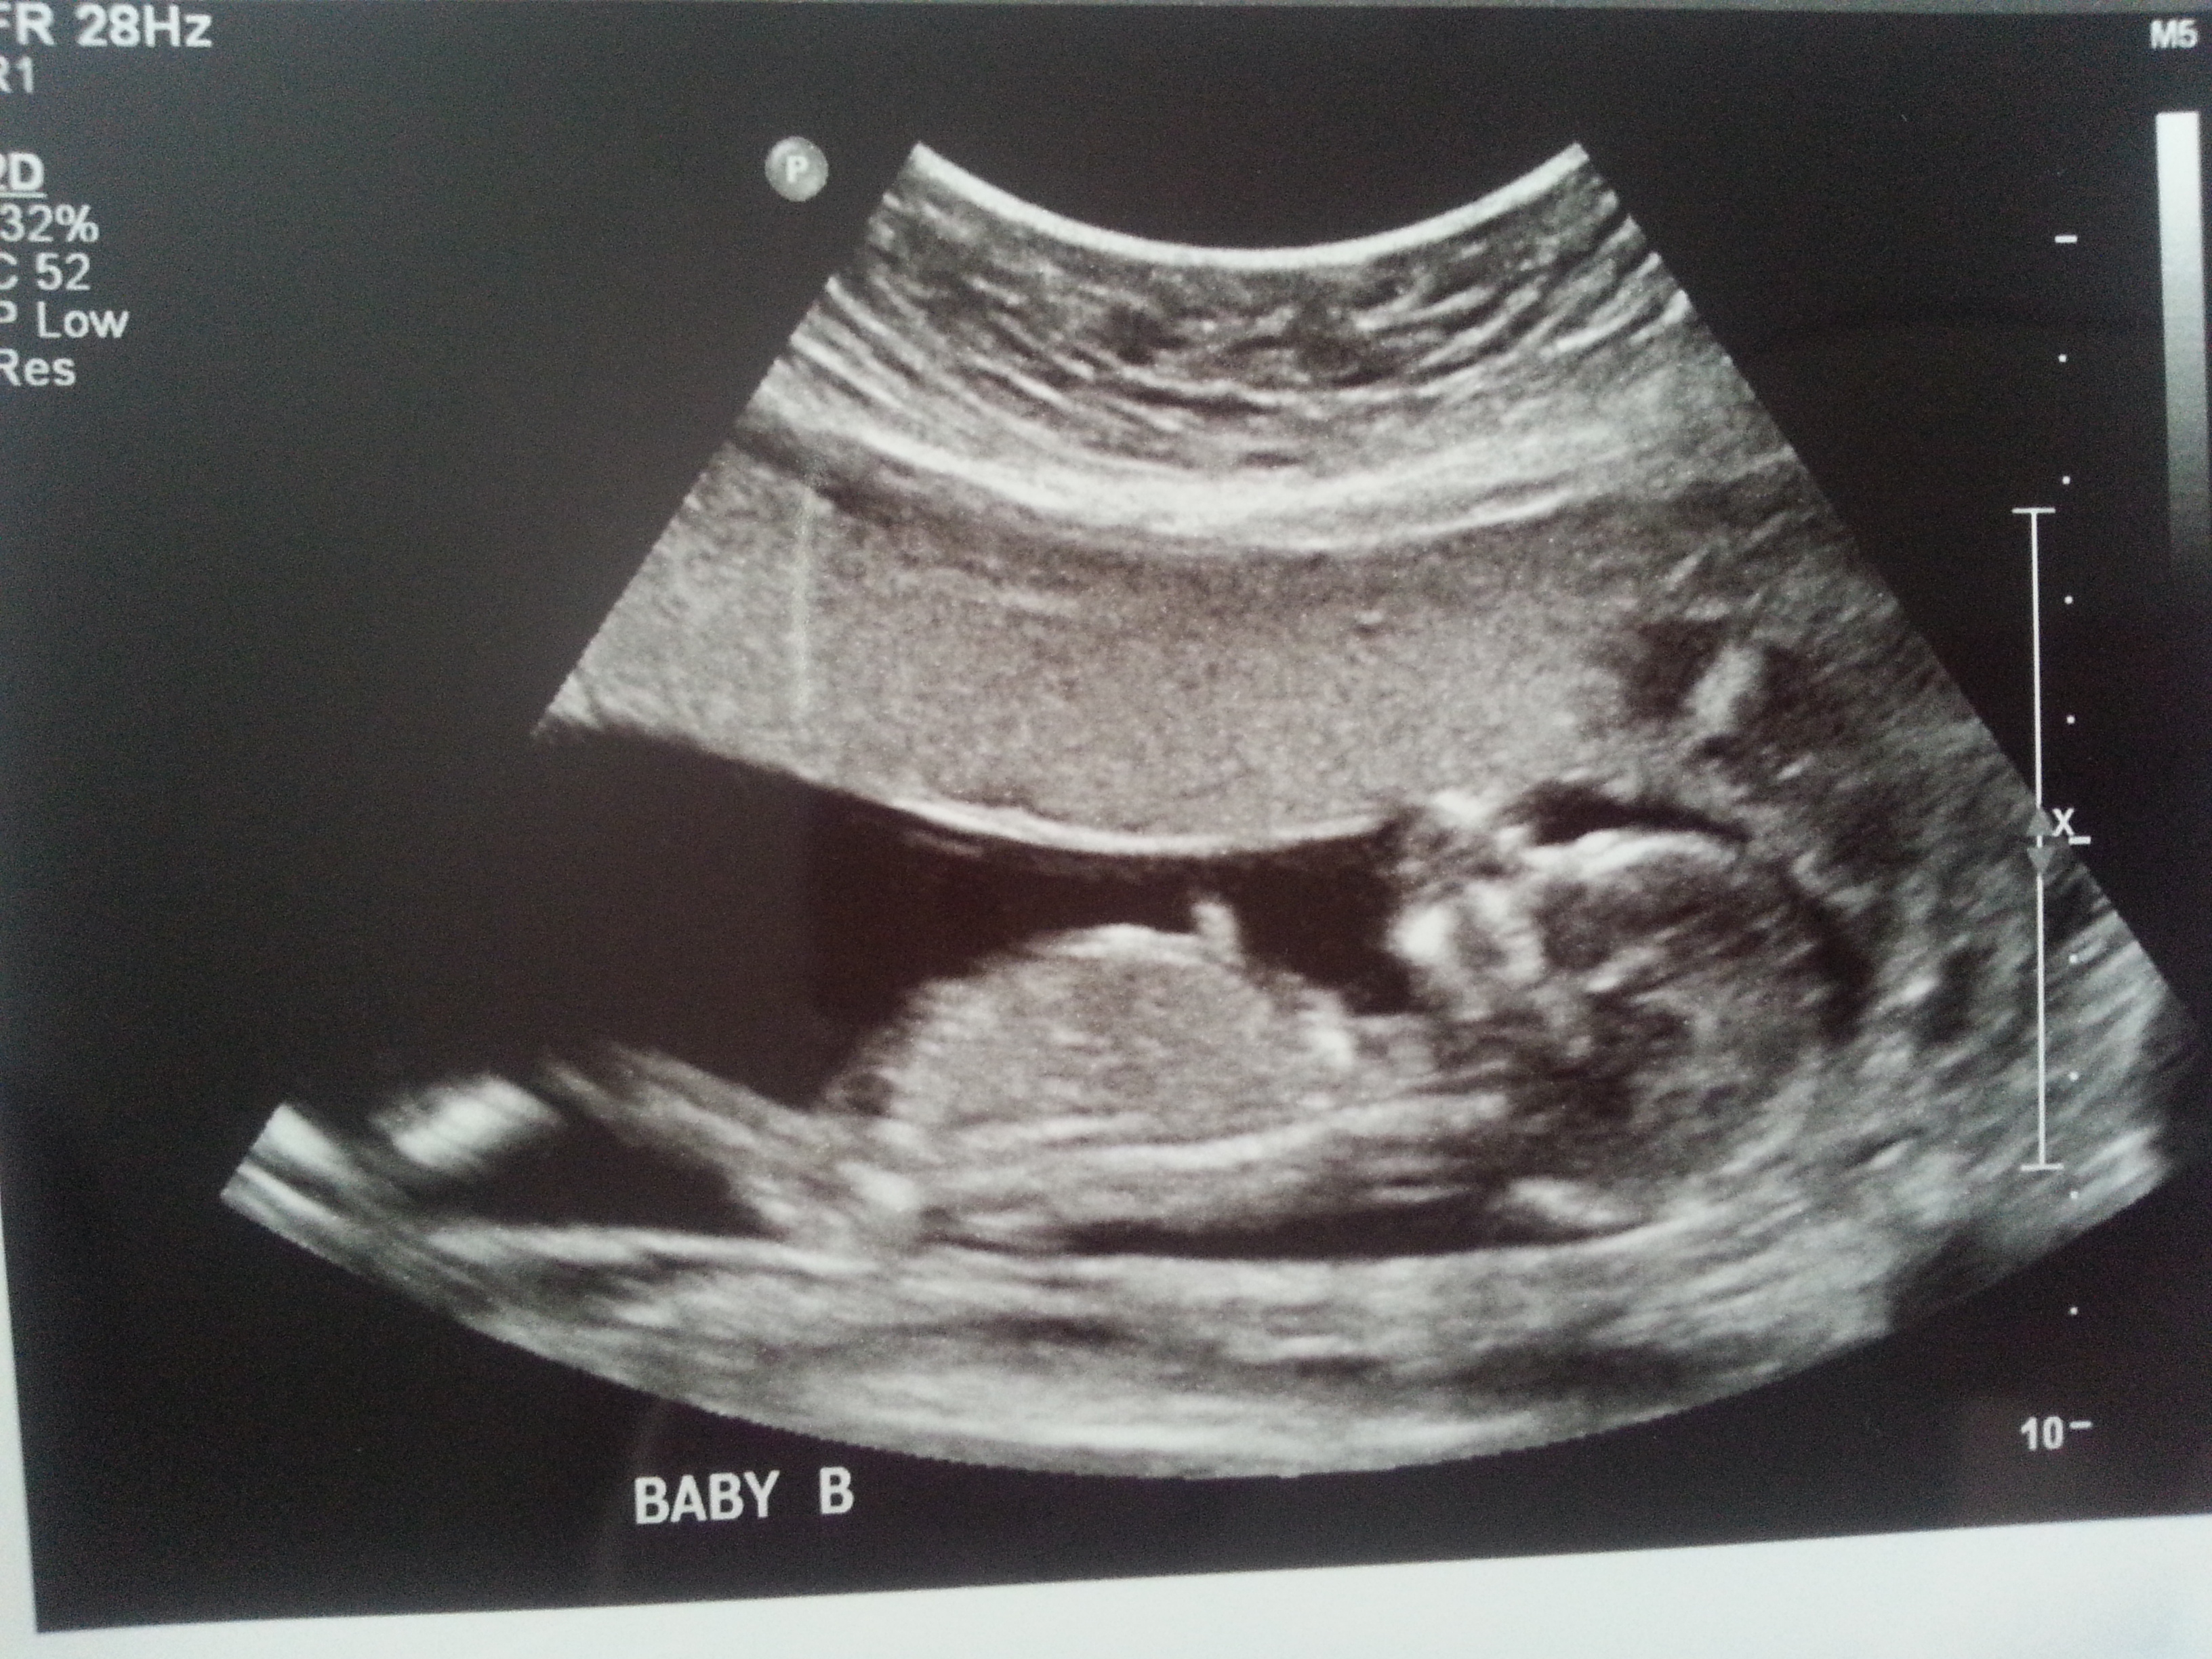

I was 12weeks 6 days and measuring 13weeks 3 days.

Attachment 23436

Maybe boy/girl. Not the best shots though!

I think B is a boy and A is a girl.

I'd guess boy/girl too. Baby B looks really boyish. Baby A is more questionable, but at 13 weeks, I'll lean girl.

I definitely see the girly nub for baby A now thanks to Nahris post!

I think B is def a boy. A has a boyish skull but girly nub. I'd go with the nub though and lean girl! Congrats on your twins!